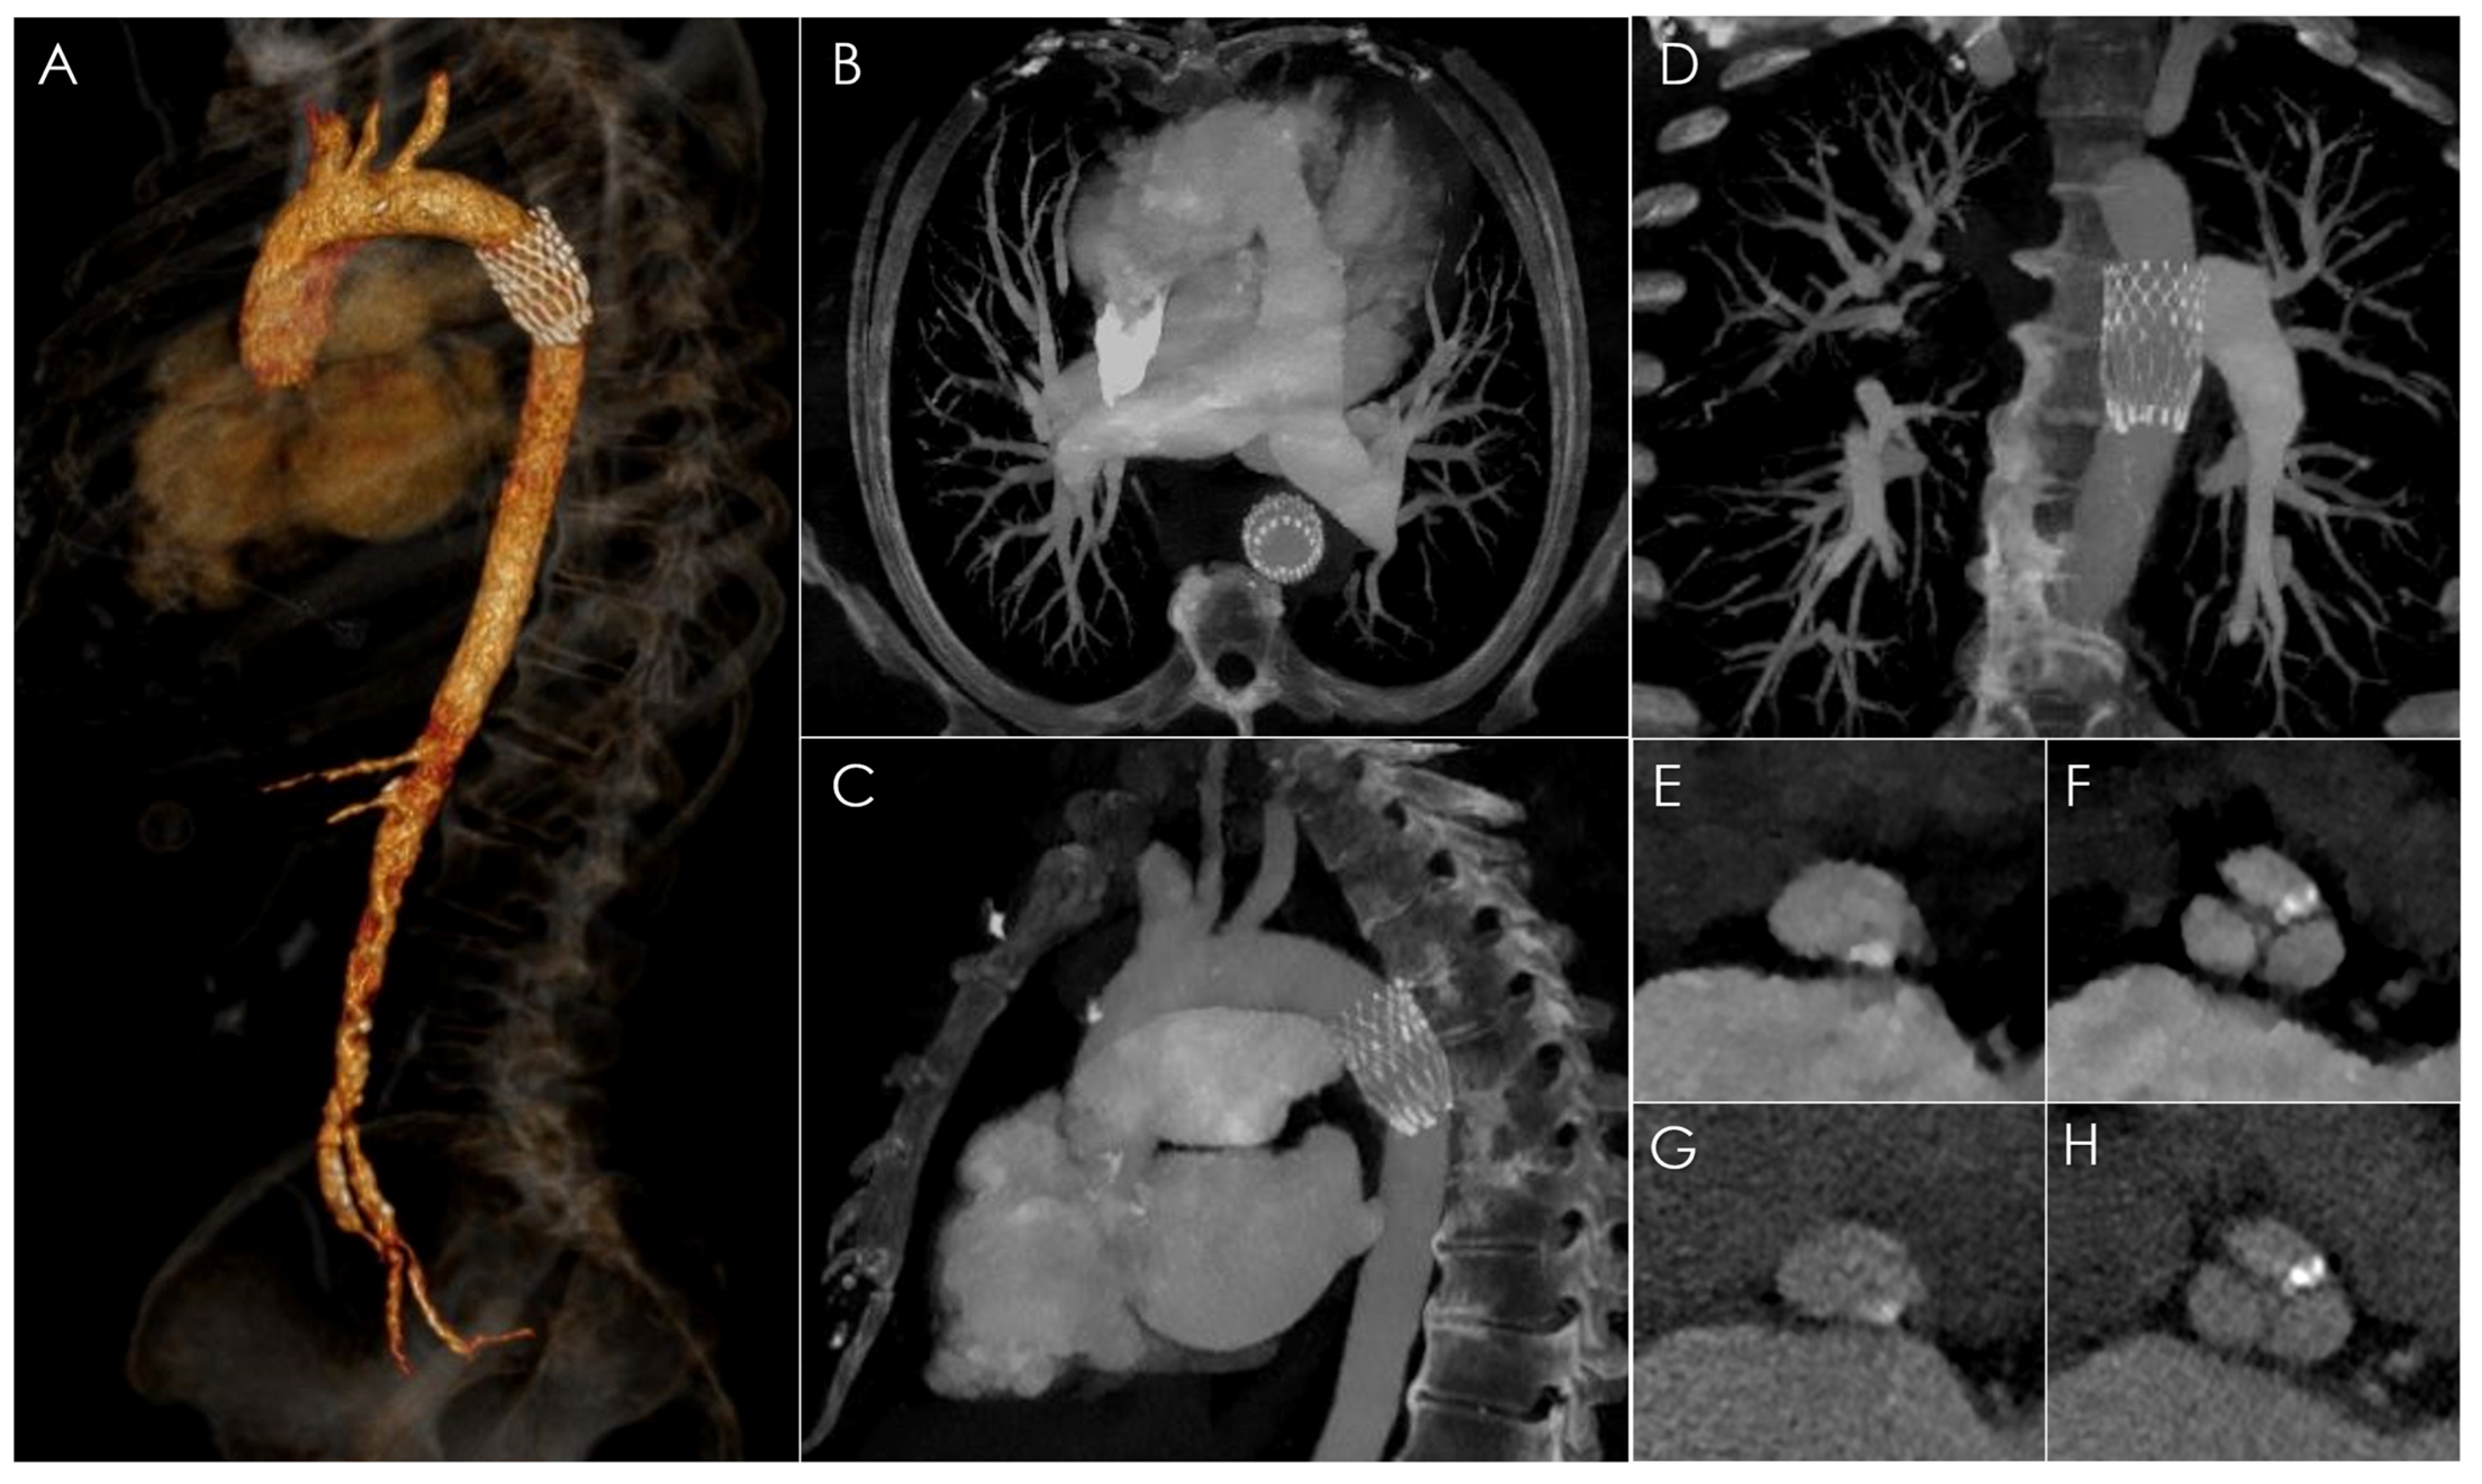

Spectral CT Imaging of Prosthetic Valve Embolization after Transcatheter Aortic Valve Implantation

D’Angelo, T.; Vizzari, G.; Lanzafame, L.R.M.; Pergolizzi, F.; Mazziotti, S.; Gaeta, M.; Costa, F.; Di Bella, G.; Vogl, T.J.; Booz, C.; et al. Spectral CT Imaging of Prosthetic Valve Embolization after Transcatheter Aortic Valve Implantation. Diagnostics 2023, 13, 678. https://doi.org/10.3390/diagnostics13040678